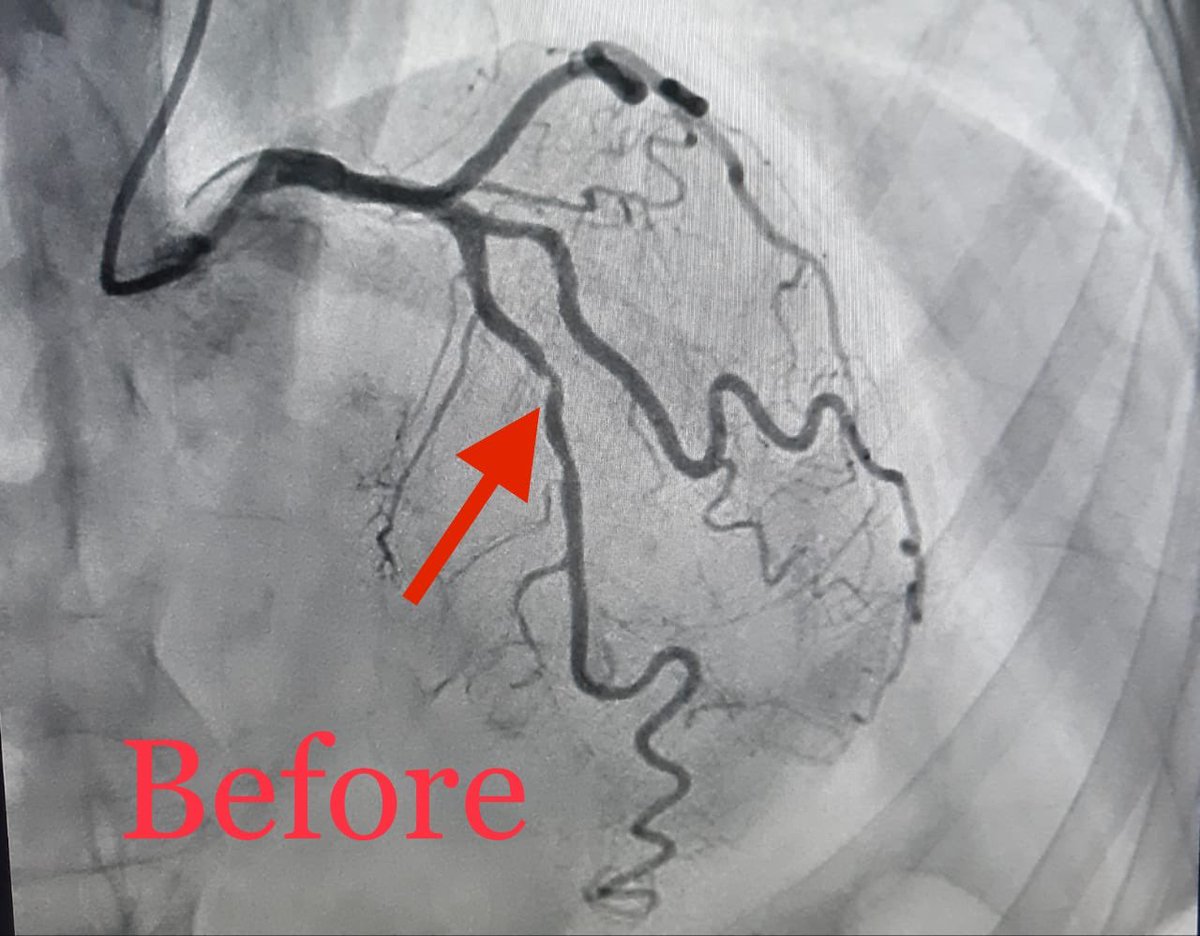

تعاملنا اليوم مع احدى الحالات من هذه الفئة العمرية العزيزة على قلوبنا، مريضة ثمانينية حضرت للطواري باعراض غير نمطية لتصلب الشرايين، تم تشخيصا و علاجها و لله الحمد